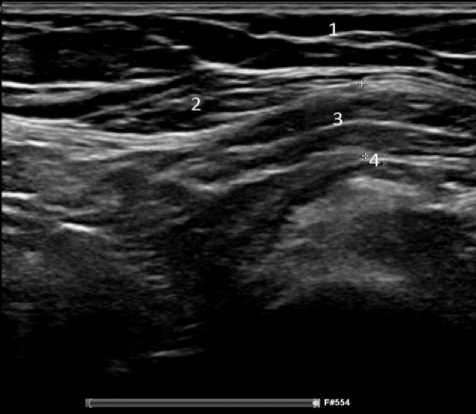

Обследование 242 пациентов показало, что диагностика паховой грыжи у мужчин не сложна. Клинические проявления заболевания позволяли во время осмотра установить диагноз, а при УЗИ оценить состояние тканей в паховых областях, локализацию грыжи (прямая или косая) и определить содержимое грыжевого мешка, что имело значение для установления сроков выполнения операции. У женщин были проблемы ранней диагностики неосложнённой грыжи при астеническом телосложении и у гиперстеников, страдающих ожирением. На ранних сроках развития грыжи женщины предъявляли жалобы на боли в паху при отсутствии над ним опухолевидного образования. При этом из-за особенностей расположения наружного отверстия пахового канала в проекции половых губ определить грыжу при пальцевом исследовании было не всегда возможно. Объяснить эту особенность можно тем, что при косой паховой грыже, спускающейся через глубокое паховое кольцо, грыжевой мешок расслаивает круглую связку матки, имеющей малый диаметр, не выходит за её размеры. При прямой паховой грыже грыжевой мешок смещается параллельно круглой связке матки, подходит к наружному паховому кольцу и располагается под ним в виде опухолевидного образования, что позволяет клинически поставить диагноз. У пациенток с ожирением из-за избытка жировой ткани в надлобковой области определить грыжевой мешок при отсутствии клиники ущемления, выходящий из наружного отверстия пахового канала, практически очень сложно, что для установления диагноза требует применения инструментальных методов исследования. Применение УЗИ позволяло установить и подтвердить диагноз у пациентов с паховой грыжей. На рисунках 1 и 2 представлены результаты УЗИ у пациента Н., 37 лет, с двухсторонней паховой грыжей, которые позволили подтвердить диагноз и выполнить операции по поводу паховых грыж открытым способом с двух сторон. На рисунке 3 представлены результаты УЗИ пациентки Н., 45 лет; диагноз – правосторонняя косая паховая грыжа: вид грыжевого мешка, расположенного в круглой связке матке.

Рисунок 2. Пациент Н, 54 года. Изображение прямой правосторонней паховой грыжи при ультрасонографическом исследовании: 1 — подкожно-жировая клетчатка; 2 — наружная косая мышца живота; 3 — грыжевой мешок

Figure 2. Patient H., 54 years old. Ultrasonographic image of a direct right-sided inguinal hernia: 1 – subcutaneous fat; 2 – external oblique abdominal muscle; 3 – hernial sac